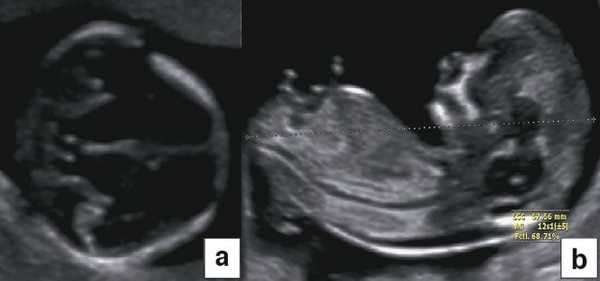

Визуализация эмбриона впервые возможна при трехмерном исследовании плодного яйца сроком не менее 3-4 недель, эмбриональные стадии имплантации визуализировать не удается. Дифференцировать зародыш на трехмерном УЗИ можно на стадии "первичной полоски", начиная с 9-й сомитной стадии [3], когда размер зародыша достигает 1,35 - 1,5 мм (4 недели гестации). На этом этапе можно рассмотреть амниотическую полость, зародыш в виде "рисового зернышка" и прикрепляющий стебелек. Эхографическая дифференциация головного и тазового конца, внутризародышевых структур еще невозможна (рис. 1).